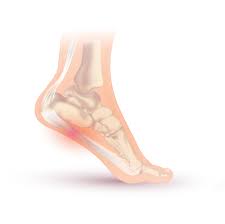

족저근막염은 발바닥을 덮고 있는 근막인 족저근막에 염증이 생겨 발생하는 질환이며, 다음과 같은 증상이 나타날 수 있습니다.

- 발바닥 아치 부위의 통증: 가장 일반적인 증상 중 하나로, 발바닥 아치 부위에 심한 통증이나 불편감이 나타납니다.

전형적인 증상은 아침에 일어나 처음 발을 디딜 때 느껴지는 심한 통증이 특징적이지만, 모두 같은 증상을 겪는 것은 아니다. 통증은 주로 발꿈치 안쪽에 발생하는 경우가 대부분이고 발뒤꿈치뼈 전내측 종골 결절 부위를 누르면 통증이 발생하기도 한다. 발가락을 발등 쪽으로 구부리면 통증이 심해지기도 한다.